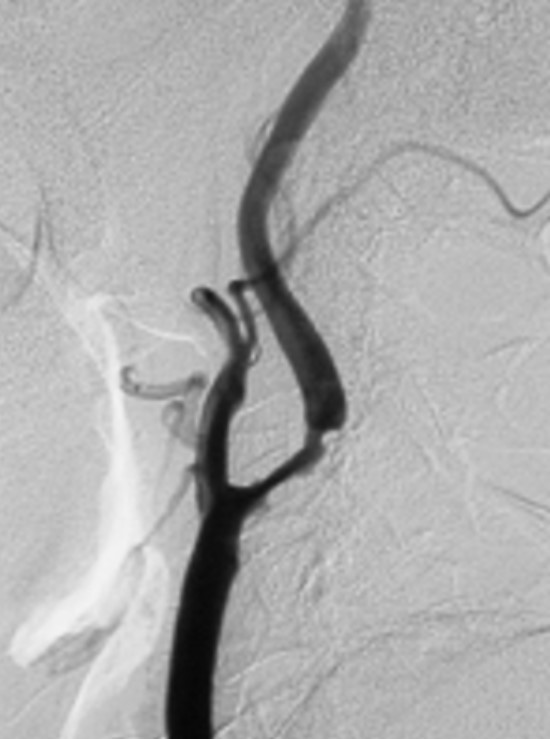

Figure 1: Preoperative DSA right common carotid arteriography lateral view of a 74-year-old man with cerebral infarction who developed moderate left hemiparesis and left homonymous hemianopsia. Severe stenosis of 71% was observed at the origin of the right internal carotid artery, and we considered that surgery for CEA was indicated. (NASCET method for calculating the stenosis rate = minimum diameter of blood vessel at stenotic part of internal carotid artery ÷ diameter of blood vessel at distal part of stenotic part) More than 100% vasodilation was obtained with CEA (Figure 2).

Figure 1